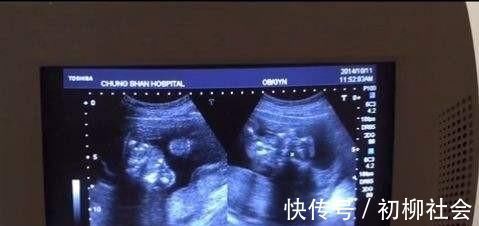

而昨天,却出了点小意外。孕24周的陈女士像以往那般去产检,今天之前的医生正好轮休,换成一个年轻医师来产检。

“怎么会这样,孩子一直做鬼脸。”陈女士听到医生这句话,有些得意,想着自己孩子这么小就调皮,还与医生开玩笑道,“这孩子长大以后一定很聪明。”

“一直做鬼脸并不是值得高兴的症状,你先起来,下午再来检查一次。我刚刚已经试了很多次,一直都有些异常,暂时还不能分析出来。”

好不容易熬到下午,再次做了彩超。下午之前轮班的医生回来了,了解完上午的情况,并看了报告,一切都得到了落实。原来,上午那番“异常”是孩子动的太厉害,彩照照的太模糊,再加上年轻医师经验不足,才认为是“异常”。